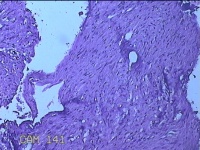

右膝部皮肤肉芽肿

性别

男

年龄

13岁

临床诊断

皮肤肉芽肿

一般病史

外伤后,出现右膝部皮肤肉芽肿形成。

标本名称

大体所见

灰白暗红色带皮肤样组织2.8x1.8x1.3cm,表面糜烂,切面灰白粉红色,质软。

图4